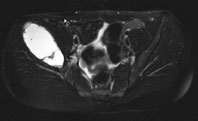

Ein 13-jähriges Mädchen kommt humpelnd zu Ihnen in die Praxis mit Schmerzen in der rechten Hüfte, die seit einigen Monaten bestehen und besonders bei Belastungen auftreten. Eine sichtbare Schwellung besteht nicht, kein Sturzgeschehen in der Anamnese.

Die Röntgenuntersuchung von Becken/Hüfte zeigt eine septierte geographische Osteolyse in der Ala und im Korpus des Os Iliums rechts. Das Röntgenbild und die Aufnahmen der nachfolgenden MRI-Untersuchung sehen Sie hier:

T2 FS, coronar, 5 mm

Bild vergrössern